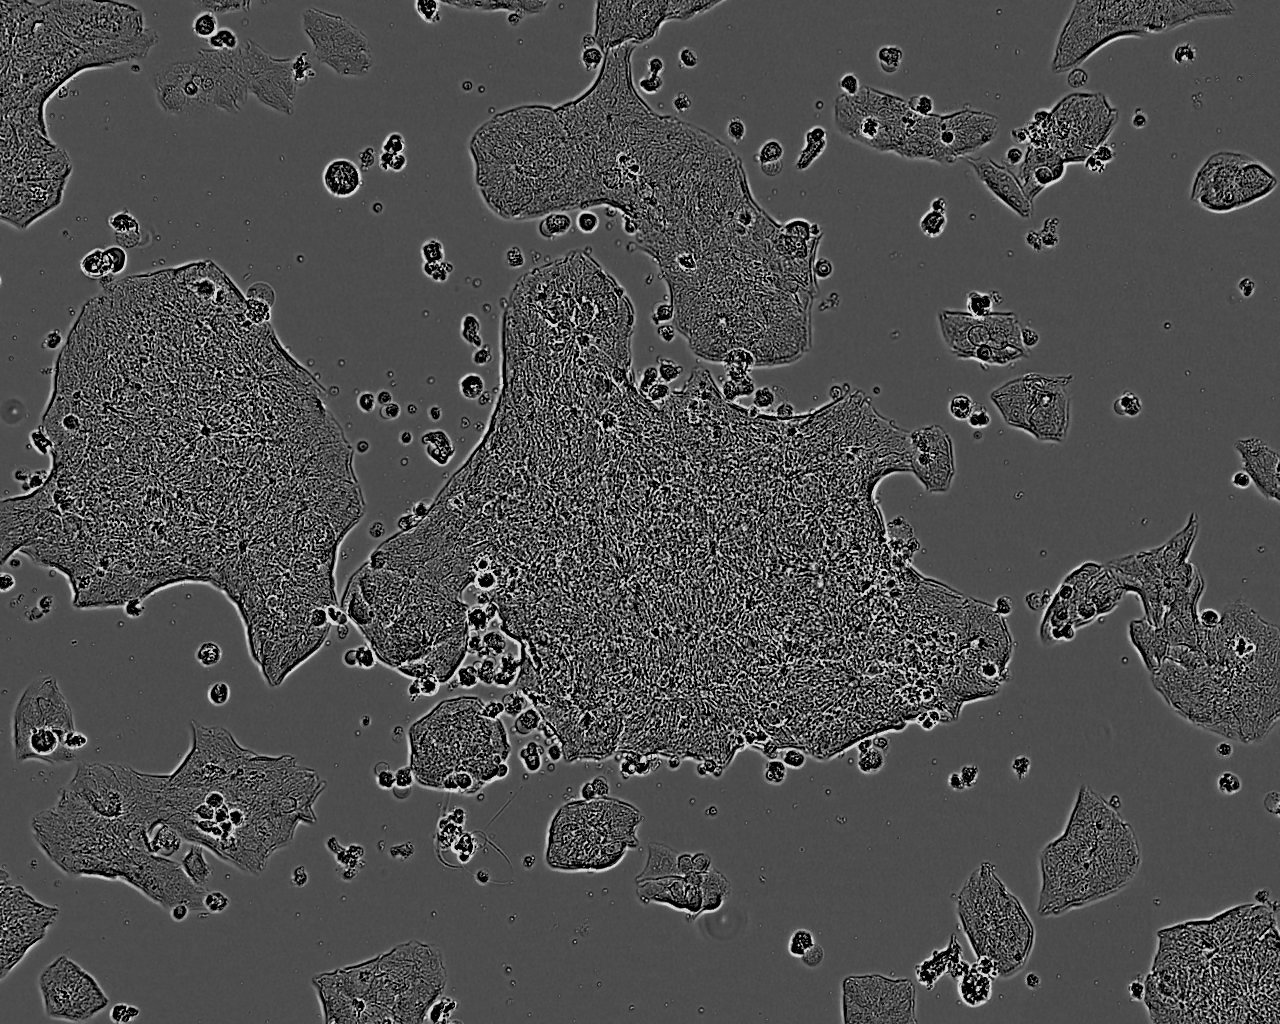

HEp-2:人喉表皮样癌复苏细胞(提供STR鉴定图谱)

细胞生长:贴壁

细胞背景资料:最初认为这个细胞源自喉上皮癌,但随后通过同功酶分析、HeLa标记染色体和DNA指纹分析发现,起源细胞已被HeLa污染。 角蛋白免疫过氧化物酶染色阳性。

细胞形态:上皮细胞样

细胞生长特性:贴壁生长